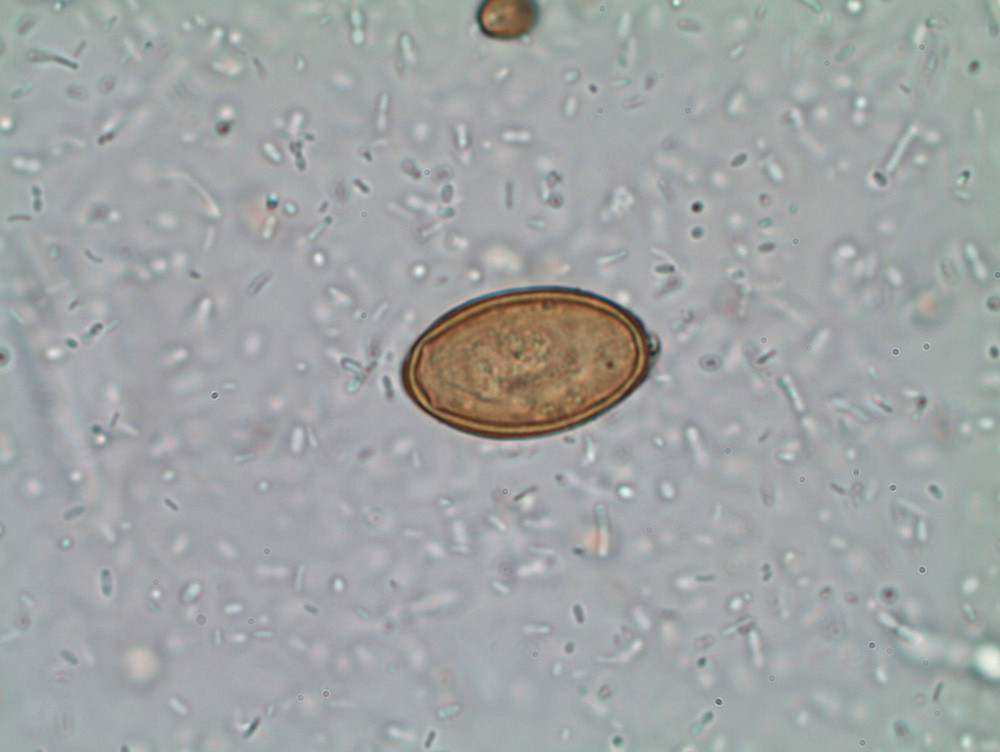

Pasienten ble derfor henvist til koloskopi med tanke på kolitt, og det ble sendt inn to avføringsprøver til mikroskopi for undersøkelse med tanke på parasitter. Mikroskopien viste små egg som, på bakgrunn av størrelse, form og reisen til det nordafrikanske landet, ble bestemt til å være fra en liten tarmikte (trematode): Heterophyes heterophyes. Pasienten fikk dagen etter poliklinisk time ved universitetssykehus.

Eggene fra Heterophyes er små, ovale og brune, med embryo og operculum/lokk. De er 28 – 30 μm lange og 15 – 17 μm brede og likner egg av andre humanpatogene ikter (f.eks. arter av Clonorchis, Opisthorchis og Metagonimus (13). De skiller seg fra opisthorchisegg ved at de er mer ovale med mindre markant operculum (mangler «skuldre») og er uten ytre utydelig lag. Immunologiske og serologiske tester som kan bekrefte diagnosen er stort sett bare brukt i forskningssammenheng.